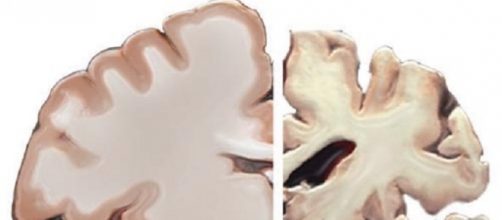

The physical manifestations of Alzheimer’s consists of neural tangles and plaques that interfere with the brain’s ability to function. The decline is slow but inexorable. First memory starts to go, then intelligence, and then the sufferer is an empty shell, robbed of self-identity, entirely dependent on others for daily existence. Alzheimer’s has blighted both the famous, such as former President Ronald Reagan and actor Charlton Heston, and the ordinary.